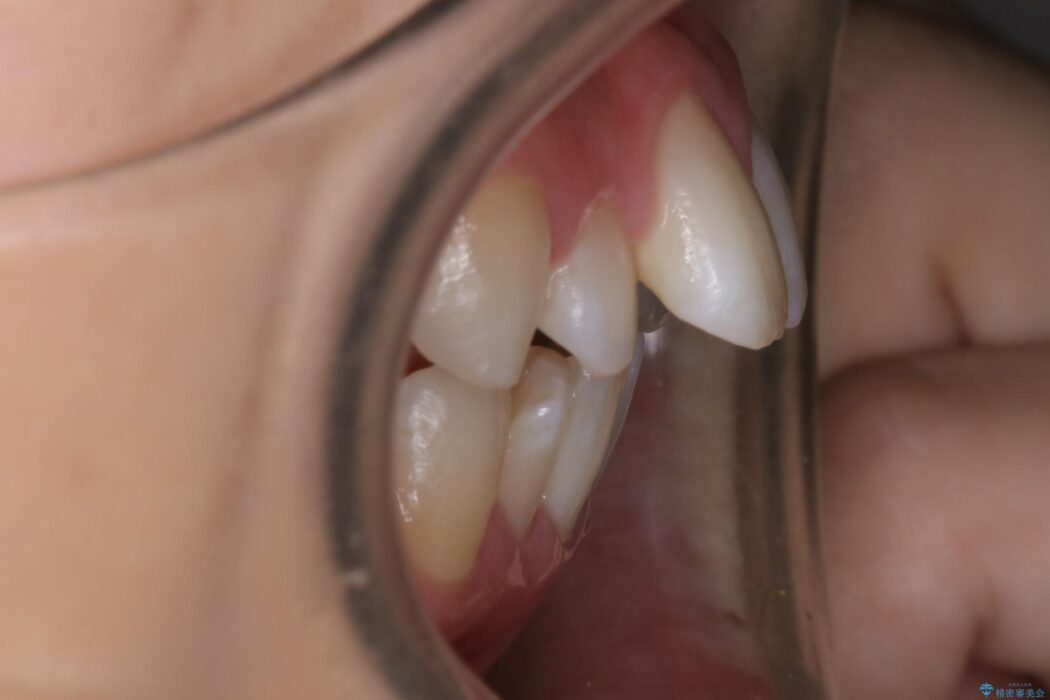

前に出ている口元を下げたいとの主訴で来院されました。

検査したところ歯に対して骨が上顎・下顎共に小さいことがわかりました。

それによりスペースが少なく歯列がガタついたり前方傾斜する生え方となっていました。

顔貌のビフォーアフターでもわかるように口元の出っ張りが改善され、患者様にはとても喜んでいただけました。

横顔であったり笑った時の印象にも変化があるため、同様のお悩みを抱えている方はぜひご相談ください。